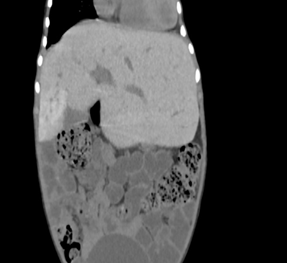

Abdominal

and pelvic ultrasonography in this patient demonstrated hepatomegaly with the

liver measuring 14.7 cm, with enlarged left lobe and normal echogenicity.

Cholelithiasis was consistently present, with gallstones measuring up to 6 mm

on follow-up, contained within a normally distended gallbladder with normal

wall thickness.

The pancreas

showed interval development of hyperechoic echotexture, potentially reflecting

iron deposition or early diabetic changes, correlating with the newly diagnosed

diabetes mellitus noted in the clinical history. Notably, the study

reproductive system abnormalities including an infantile uterus (corpus length

1.7 cm, AP diameter 0.3 cm; cervix length 1.7 cm, AP diameter 1.3 mm) and

bilateral streak ovaries (right: 0.7 x 0.1 cm, left: 1.0 x 0.1 cm), consistent

with hypogonadotropic hypogonadism secondary to iron overload affecting the

hypothalamic-pituitary-gonadal axis (Figure

3).